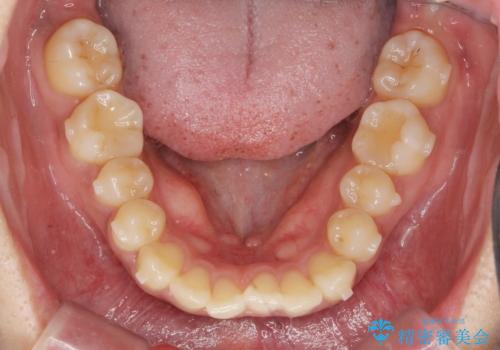

前歯のがたつきをすっきり マウスピース矯正

しっかりと前歯のがたつきは改善し見た目が大きく良くすることができました。

- 1年2ヶ月

- 10-30回